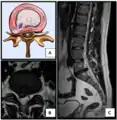

![]() تصوير فتق القرص الفقري من خلال التصوير بالرنين المغناطيسي. تصوير فتق القرص الفقري من خلال التصوير بالرنين المغناطيسي. | |

- اختبارات التصوير بالأشعة والتخطيط. وتشمل:

-التصوير بموجات الرنين المغناطيسي.